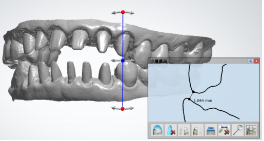

2、充分运用仿生学美学修复技术,患者修复后的咬合关系和整体美观与协调性反复的进行数字化模拟。

Cad软件预先设计排牙 设定内冠锆边 准备回切

内冠回切并最终设计完成